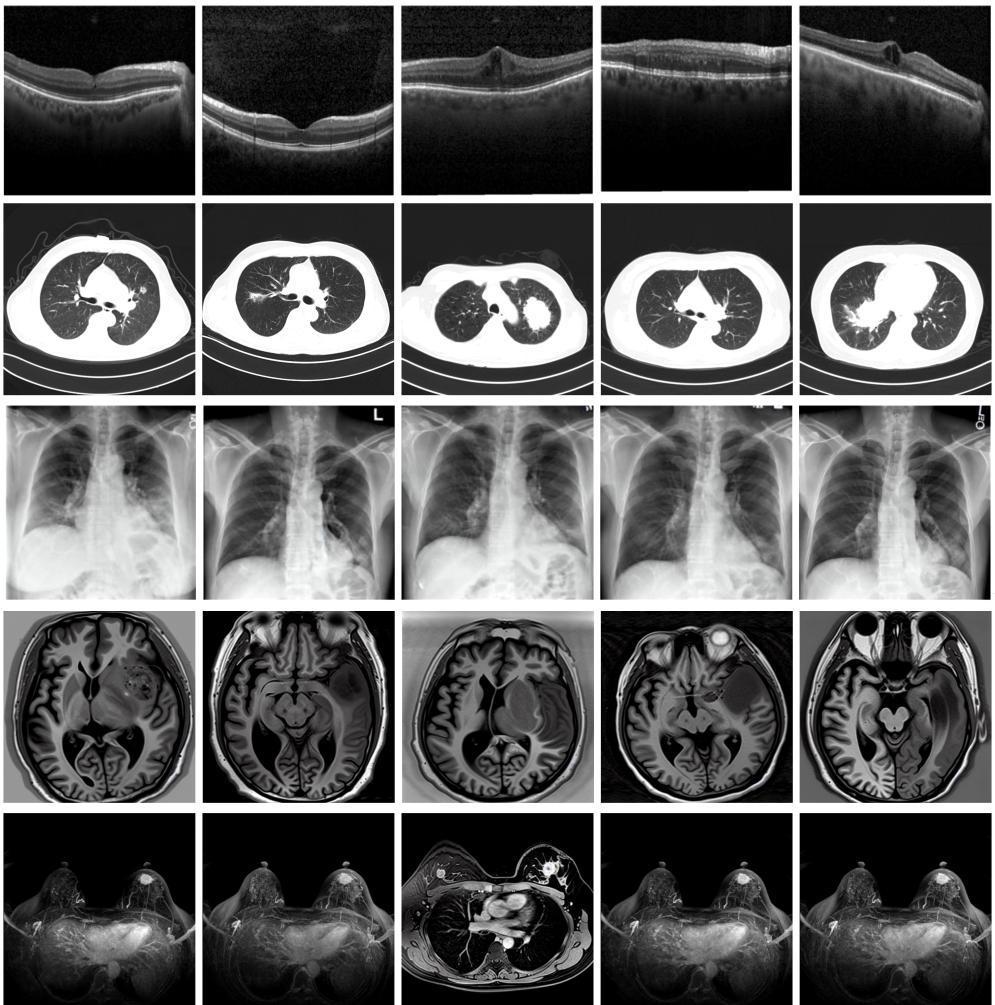

图为由MINIM生成的高质量医学合成图像(受访者供图)

“目前公开的医学影像数据非常有限,我们建立的生成式模型有望解决训练数据不够的问题。”北京大学未来技术学院助理研究员王劲卓说,研究团队利用多种器官在CT、X光、磁共振等不同成像方式下的高质量影像文本配对数据进行训练,最终生成海量的医学合成影像,其在图像特征、细节呈现等多方面都与真实医学图像高度一致。

实验结果显示,MINIM生成的合成数据在医生主观评测指标和多项客观检验标准方面达国际领先水平,在临床应用中具有重要参考价值。在真实数据基础上,使用20倍合成数据在眼科、胸科、脑科和乳腺科的多个医学任务准确率平均可提升12%至17%。